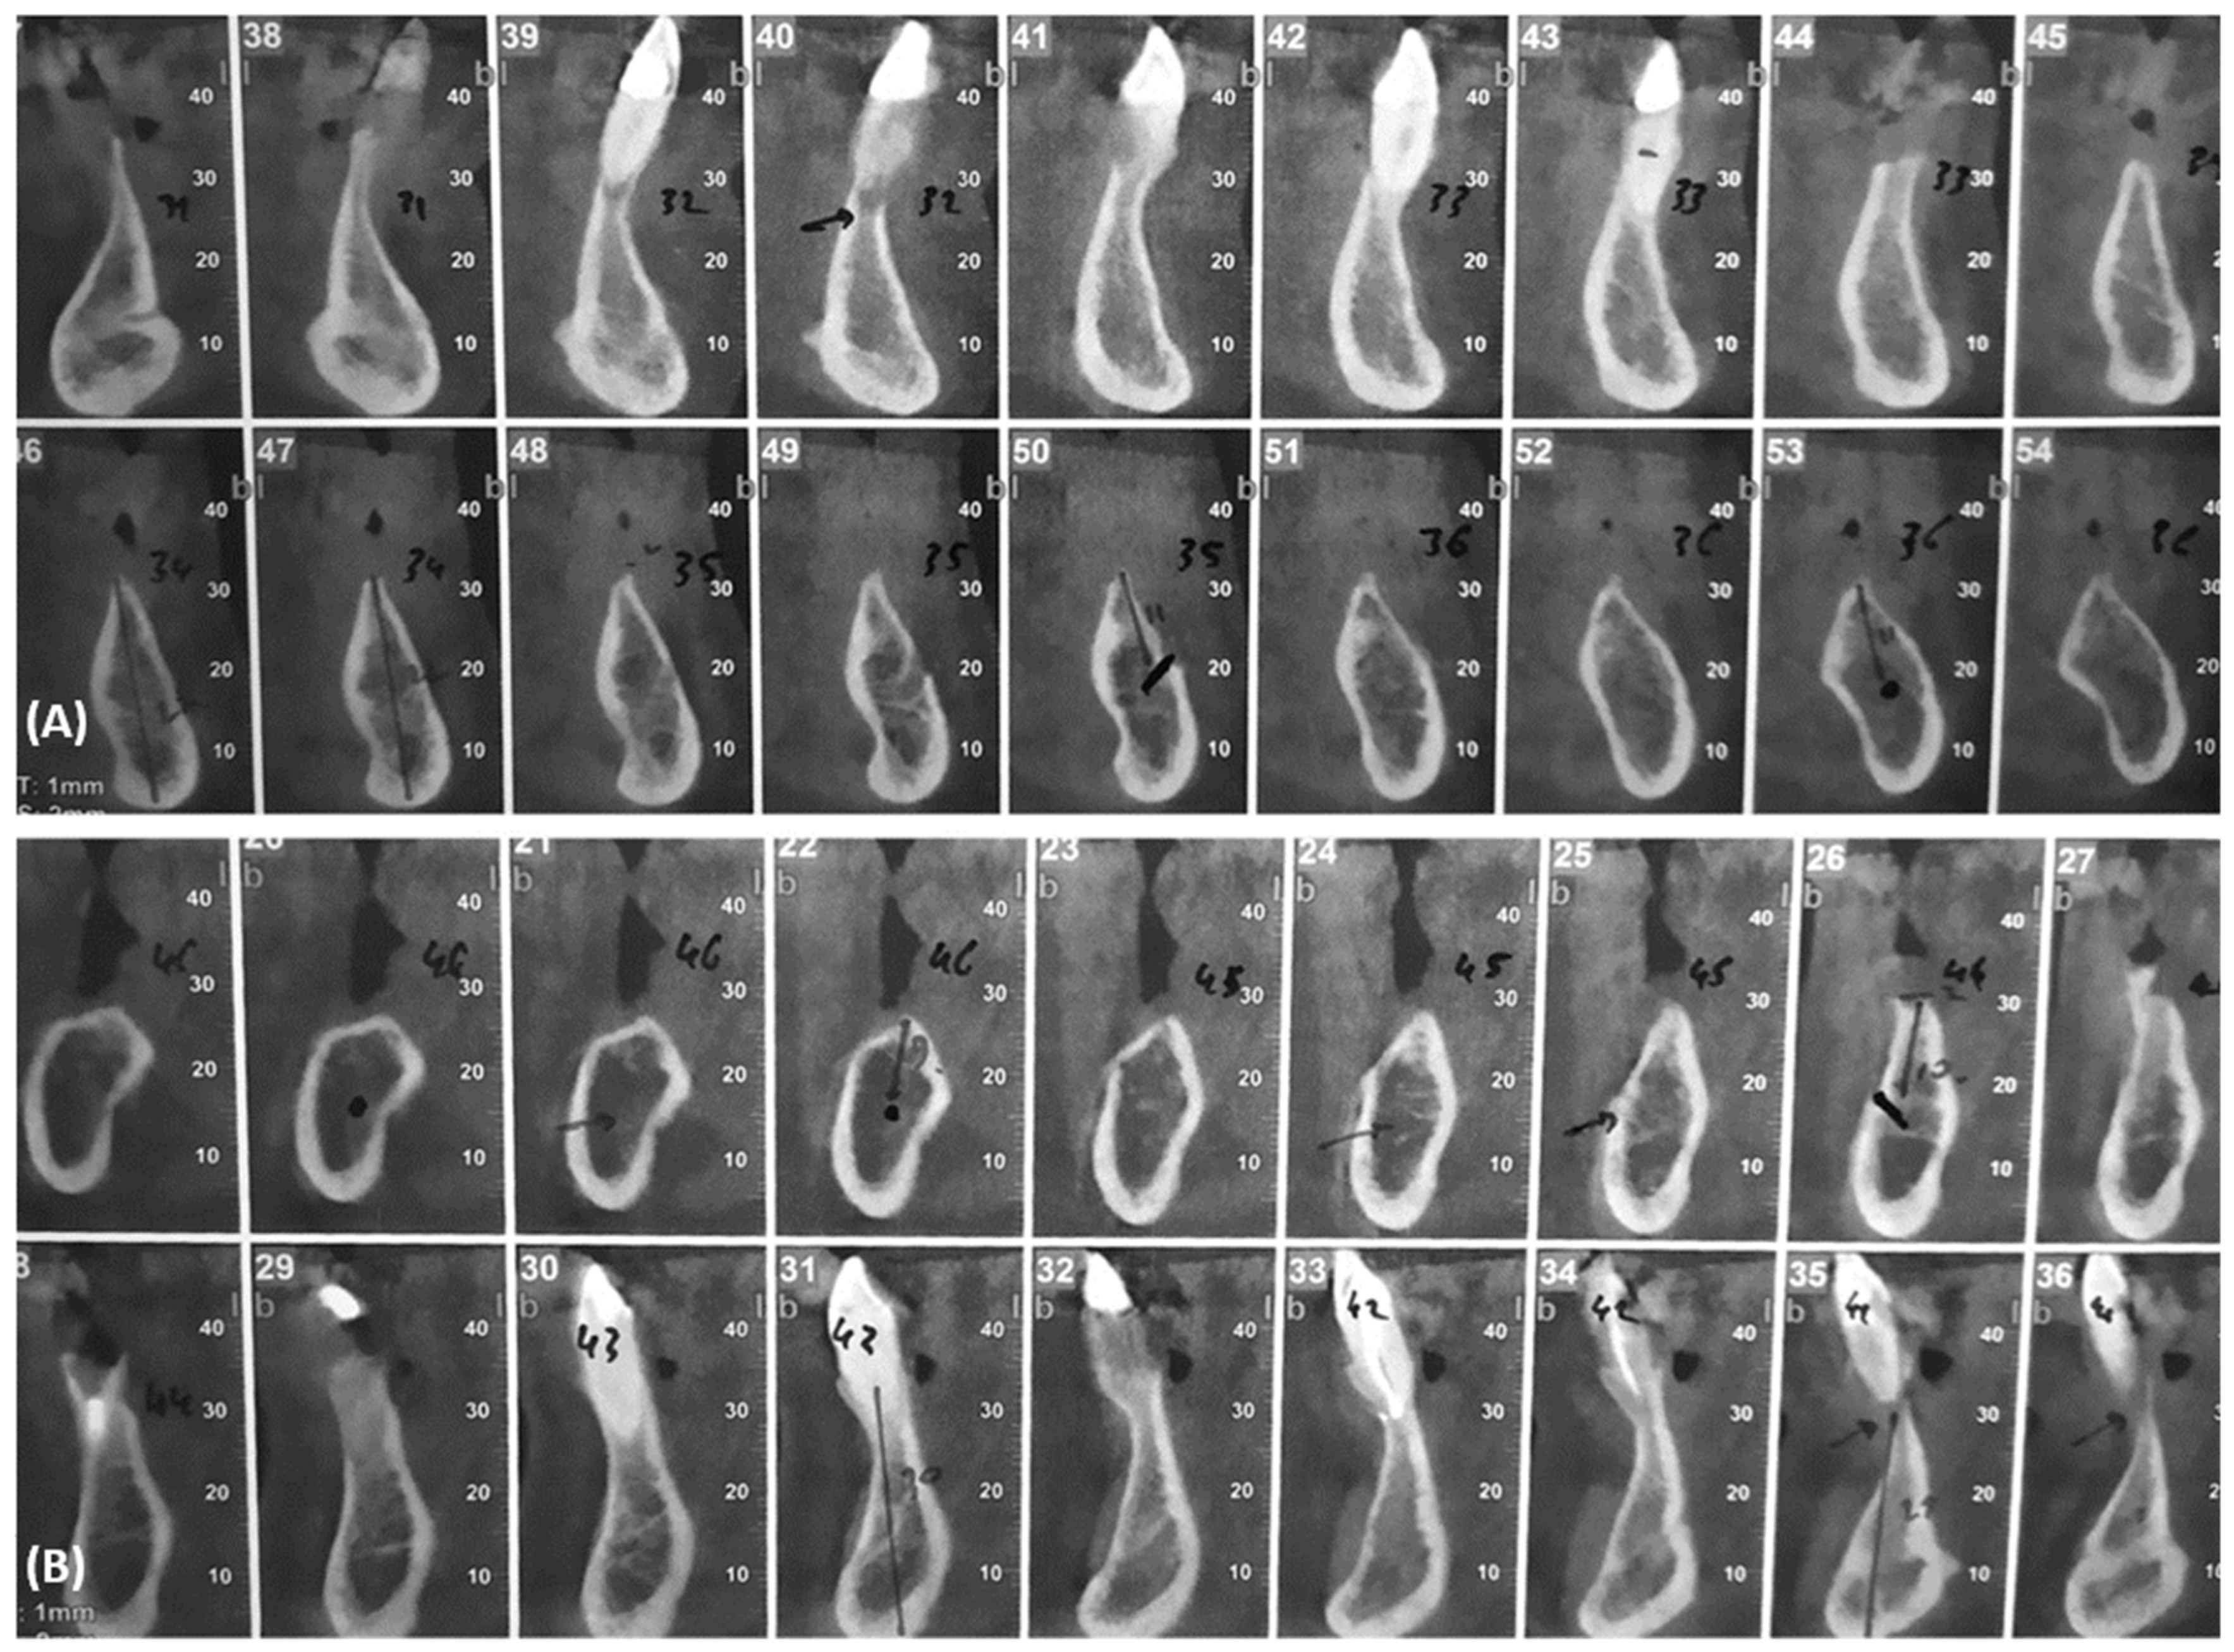

2. Case Report